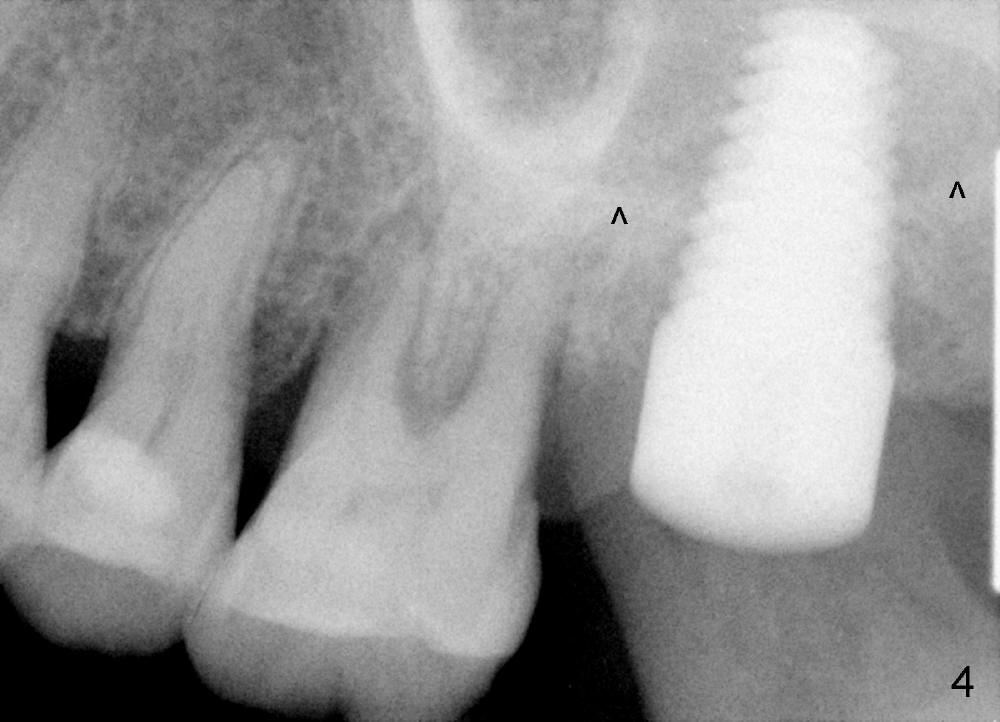

A 56-year-old female has recurrent infection and buccal gingival recession (Fig.1 *) after root canal therapy in the upper left 2nd molar (Fig.2). The extraction socket is single and large. Osteotomy forms by using a series of osteotomes (2-5 mm in diameter) mesiopalatal to the center of the socket. The sinus floor is thin (approximately 2-3 mm). The osteotomy is further enlarged by inserting 4.5-8 mm taps at the depth between 14 and 17 mm from the gingival margin. The last tap has barely achieved stability (Fig.3). It appears that the tap has almost obliterated the socket. Allograft is pushed into the sinus before placement of a 8x17 mm implant. The insertion torque is between 15 and 20 Ncm (Fig.4). The gingiva-level implant is slightly subgingival except buccal (Fig.5). To facilitate buccal gingival re-growth and cover the exposed implant surface, bone graft is placed subgingival (Fig.5 ^). The gingival sulcus is closed partially by placement of a thin strip of collagen membrane (not shown). The wound is protected by applying perio dressing.